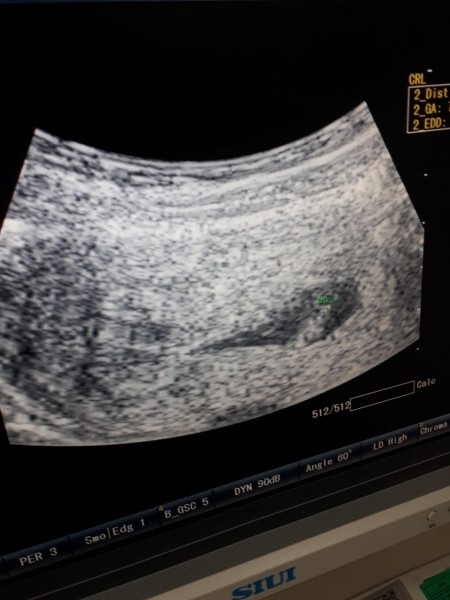

image

8+3 tahminleri alayım :)

Vajinal ultrason ise kız karından bakıldı ise oğlan kese teorisine göre gene bizim ki tahmin illa tutacak diye birşey yok :)

(748 puan)

Karından bakıldı sağlıklı olsun da hiç farketmez teşekkürler canım :)